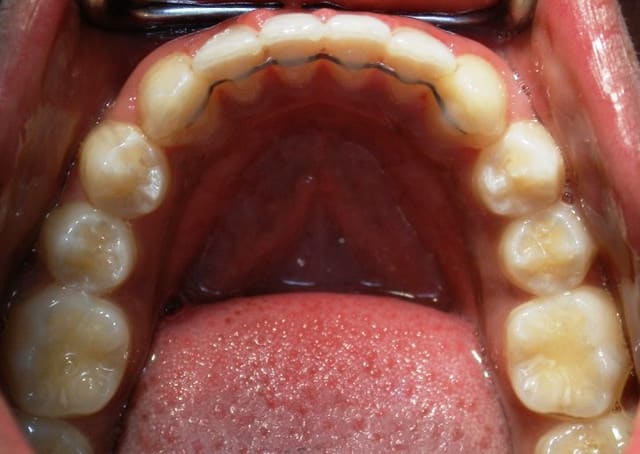

Cette chainette n’a pas besoin d’être formée à la pince comme un fil Ortho, je la trouve facile pour des confrères qui n’ont pas notre matériel

J'ai eu aussi la période gouttière..positionneur...plaque...3-3 préfabriqués...mais c'est le fil qui reste le plus fiable (compromis maintien/souplesse ) et le moins contraignant à gérer.

Au maxillaire, le plus possible de 2 à 2; sinon hawley classique.